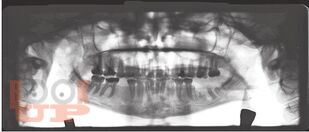

Рождение здорового ребенка зависит во многом от состояния здоровья матери. Ранее перенесенные заболевания, условия труда, прием лекарственных средств до и в течение беременности влияют на развитие плода. Эти и многие другие вопросы еще не нашли должного отражения в учебном процессе как у студентов, так и у врачей. Однако это совершенно не значит, что врач-стоматолог не должен знать их. Многие стоматологические манипуляции у беременных женщин (лечение заболеваний зубов, и их осложнений; заболеваний слизистых оболочек полости рта) проводятся с применением обезболивания, требуют лучевой диагностики и применения лекарственных средств. Своевременно и правильно оказанная помощь, а также профилактика стоматологических заболеваний повысят качество жизни будущей матери и безусловно положительно скажутся на здоровье будущего ребенка. Особенностям лечения и тактике врача-стоматолога посвящена эта работа.

Издание предназначено для студентов, курсантов и ординаторов стоматологических факультетов институтов, академий и университетов, а также для студентов лечебных и медико-профилактических факультетов. Надеемся, что эта работа будет интересна и самим женщинам, будущим мамам и молодым родителям.